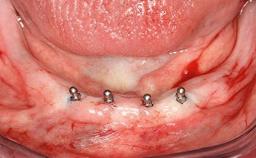

A healthy 28-year-old female patient presented for a consultation on treatment options to restore her upper right central incisor. At the clinical examination, the tooth responded to percussion and palpation. The gingiva was red and slightly swollen, with a mid-facial probing depth of 10 mm. The upper right lateral incisor showed no signs or symptoms, did not respond to exploration and percussion, and the vitality test was positive. The periapical radiograph revealed that tooth 11 had been endodontically treated, with no lesion evident at the apex. A small radiopaque calcified structure surrounded by a narrow radiolucent zone (3 × 3 mm) was present at the apex of tooth 12.

# of Implants 1

Type of Implants Two-Piece